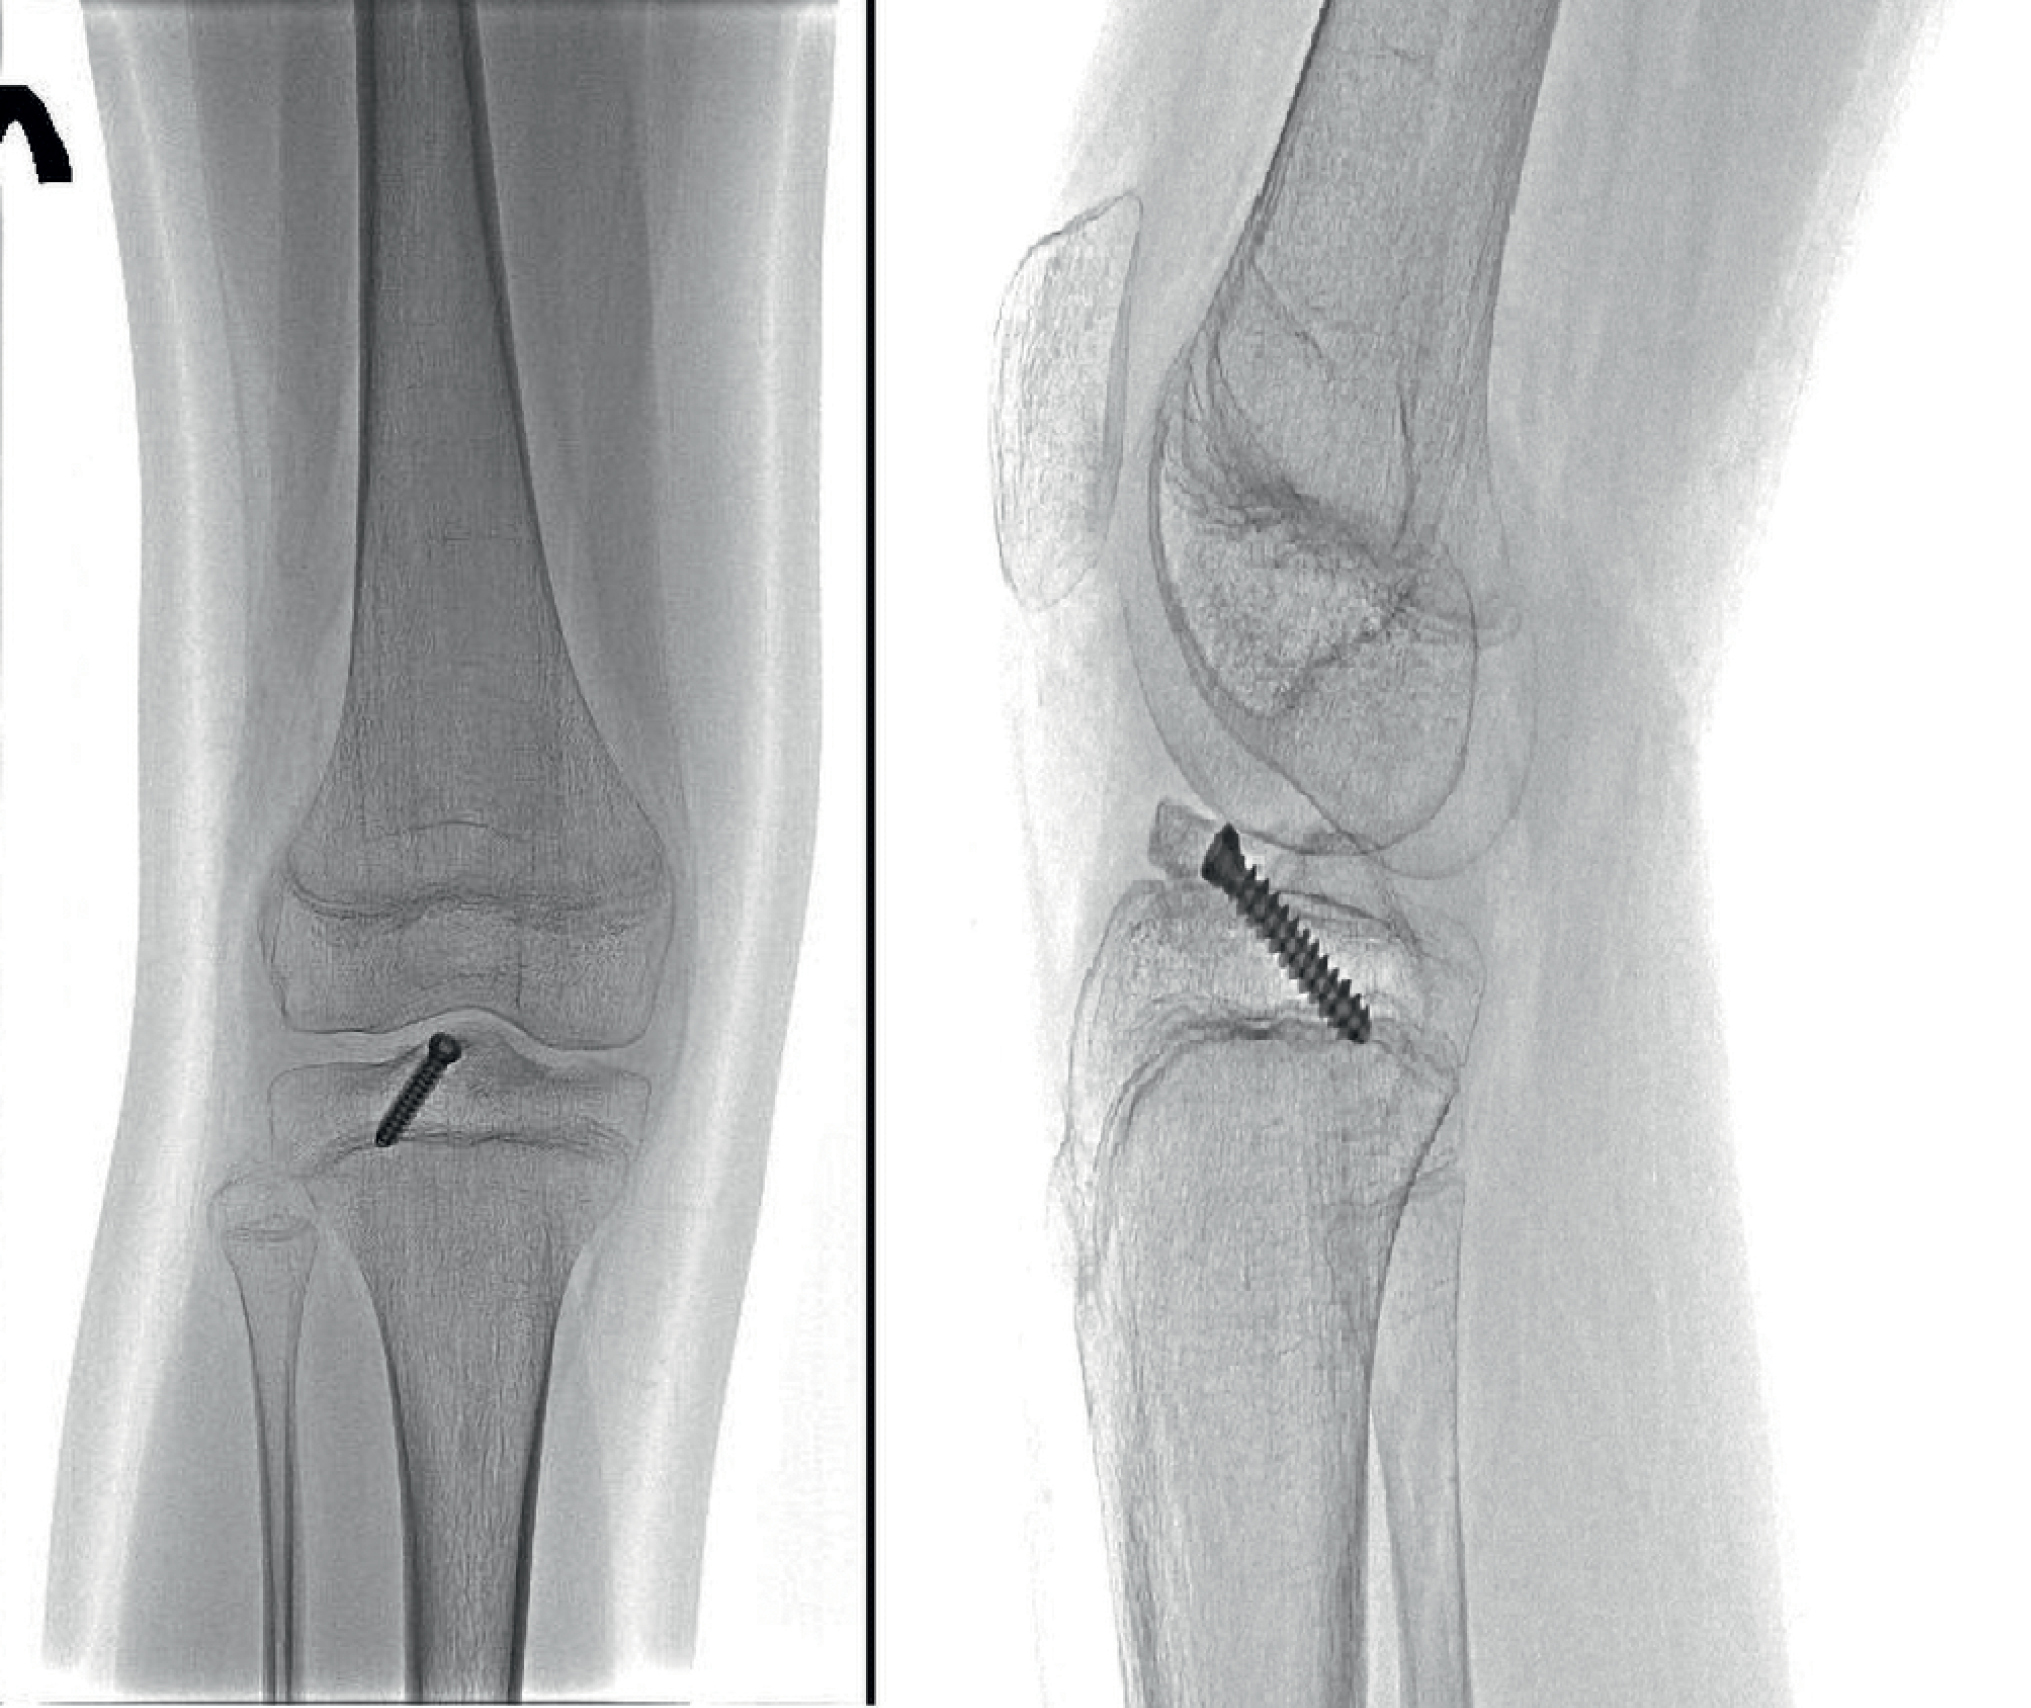

В феврале 2024 г. обратилась к ортопеду в Центр медицинской реабилитации для детей. На контрольных рентгенограммах консолидация перелома достаточная. Отмечается снижение костной плотности в метафизах бедренной, большеберцовой костей, надколеннике (рис. 1).

Рис. 1. Рентгенограммы, выполненные перед курсом реабилитации

Fig. 1. X-ray image, taken before the rehabilitation

Диагностирована разгибательная контрактура коленного сустава, рекомендована реабилитация.